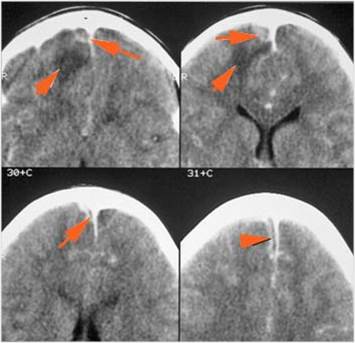

Intracranial

There is a subperiosteal fluid collection or abscess along the boney walls of the anterior or middle cranial fossa.

There is an epidural fluid collection or abscess along the boney walls of the anterior or middle cranial fossa.

There is a subdural fluid collection or abscess along the boney walls of the anterior or middle cranial fossa.

There is a subdural fluid collection or abscess along the falx cerebri or within the tentorium.

There is evidence of thrombus, thrombophlebitis or other occlusive or inflammatory process of the cavernous sinus.

There is brain edema specifically involving the frontal and temporal lobes.

There is cerebritis specifically involving the frontal and temporal lobes.

There is brain abscess specifically involving the frontal and temporal lobes.

There is likely meningitis, meningoencephalitis with complicating hydrocephalus or brain herniation.